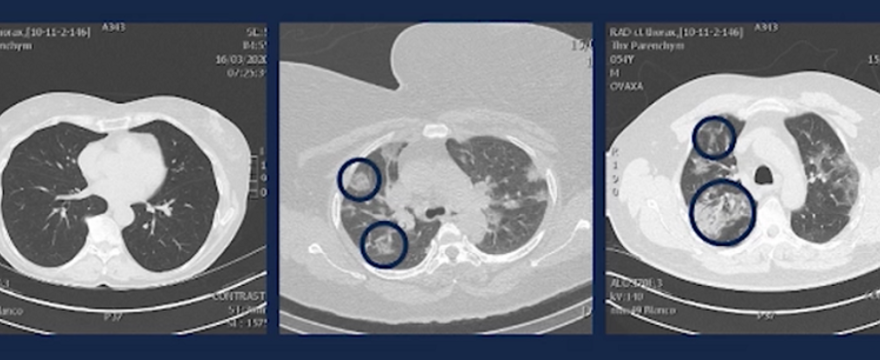

Dotychczas uważano, że koronawirus największe spustoszenie sieje wśród ludzi starszych. Tymczasem nawet młodzi ludzie w wieku 20-50 lat, muszą na siebie bardzo uważać. Mimo, że koronawirus w tej populacji wiekowej nie powoduje tak dużej śmiertelności, sieje on ogromne spustoszenie w płucach.

Po dwóch dniach zazwyczaj trafiali już na oddział z dusznościami i kaszlem – a skany ich płuc były przerażające!